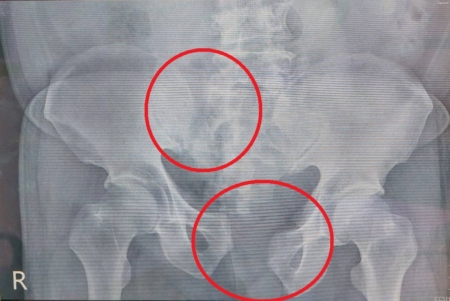

【大紀元2025年07月18日訊】(大紀元記者陳文敏台灣苗栗報導)72歲的吳先生因意外從三樓高摔落,緊急送至醫院急診,雖然當下意識清楚、血壓正常,但心跳高達150下,瀕臨休克狀態。經影像檢查發現,傷者不僅有不穩定的骨盆骨折及薦椎骨折,還有骨盆腔血管破裂出血等問題。所幸,在放射科、加護病房及骨科跨團隊合作下,吳先生順利康復出院,恢復正常生活。

大千綜合醫院骨科主任范姜治澐表示,傷者送至急診時,第一時間即啟動外傷小組團隊共同處理。因傷者下背及右大腿疼痛無法活動,加上瀕臨休克狀態,因此先以骨盆固定帶予以固定,並給予靜脈輸液及輸血來穩定生命徵象,再立即由放射科醫師進行骨盆腔血管攝影及栓塞止血,並安排於加護病房做後續照護及觀察。所幸,傷者止血後生命徵象穩定,且沒有其他器官損傷,但因骨折位移較多,需要手術復位固定,所以隔天即接受骨折復位鋼板鋼釘固定手術,術後三天轉入一般病房進行復健治療,並於一週後順利出院。